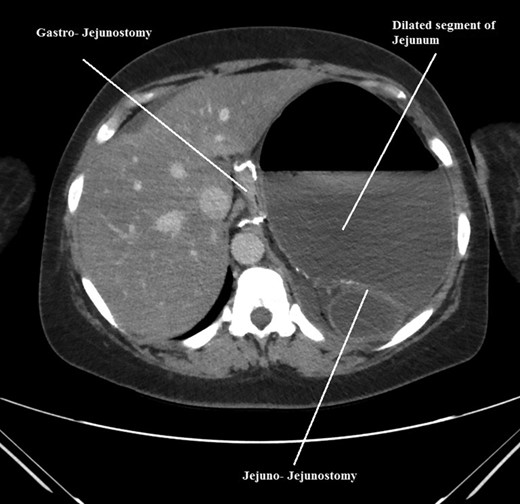

The intraoperative findings were not consistent with the radiological findings (Figs 1–4). As shown in the CT scan of abdomen and pelvis; multiple loops of dilated small bowel were seen, more predominantly dilated and matted bowel complex just above the spleen. The dilated bowel complex was decompressed using needle aspiration to help reduction of the bowel loops. The ileo cecal junction was then identified and traced back to the perisplenic hilar region. The trifurcation of three bowel loops (Roux limb, biliopancreatic limb and common limb) were identified with identification of ligament of Treitz. The prior gastric bypass was of ante colic- ante gastric type and Peterson’s defect was not closed. The above described bowel trifurcation had sunken postero- inferior to the spleen and had herniated through a potential space underneath the spleen and torsed around the splenic vessels and hilum. This picture was consistent with perisplenic small bowel volvulus. As noted earlier there was a massively dilated proximal small bowel segment above the spleen, displacing it caudally. Careful adhesiolysis was performed inferior to the spleen to release the segment of the trifurcation. The bowel segments once reduced were assessed and appeared viable. Of note, the spleen appeared better perfused after reduction. The remnant hernia defect of size 2 × 3 × 2.5 cm around the hilar region was then approximated using interrupted non-absorbable sutures. Enterotomy at the decompression site was closed with non absorbable suture. All potential sites of IH were re-examined and there was no evidence of any other internal herniation. Coelomic cavity was thoroughly irrigated and operation concluded successfully. Postoperative hospital stay was uneventful, and the patient was discharged home after two days.

Coronal CT scan of abdomen and pelvis showing Dilated jejunal segment causing caudad splenic displacement.